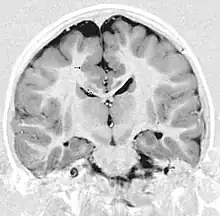

| This child presented with seizures. The coronal true inversion recovery sequence shows thickened and disordered cortex in superior frontal and cingulate gyri bilaterally (arrow). There are small convolutions visible at the corticomedullary junction. The appearance is that of cortical dysplasia, with polymicrogyria more likely than pachygyria due to the small convolutions visible. There are also small foci of grey matter signal in the corpus callosum, deep to the dysplastic cortex (double arrows). These probably represent areas of grey matter heterotopia. | |